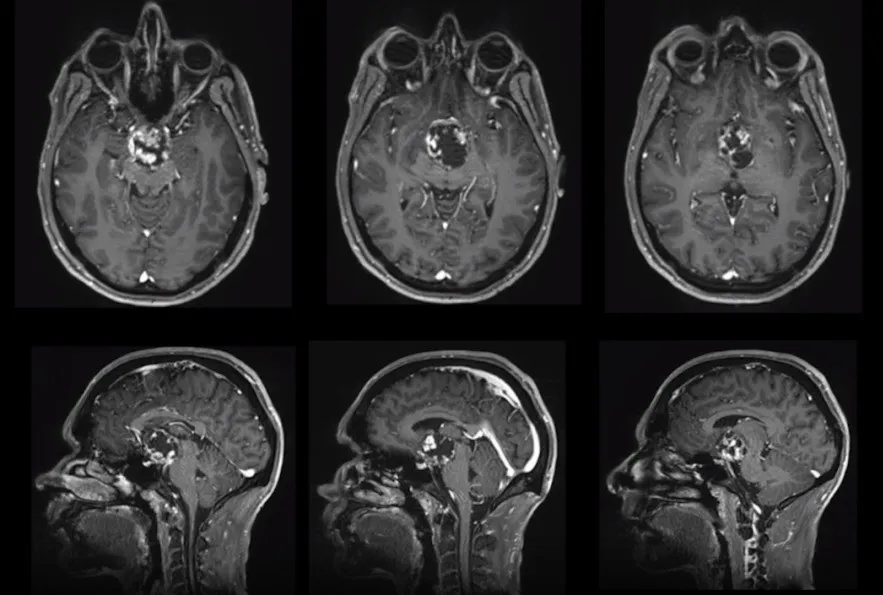

系统检查结果显示:全垂体功能减退伴轻度高泌乳素血症,内分泌系统损害明确。MRI影像进一步证实颅咽管瘤诊断,肿瘤已累及第三脑室及视神经通路,脑脊液循环通路受压,视觉功能损害持续进展,解剖毗邻关系高度复杂。

第一阶段,采用经神经内镜经鼻入路,对视交叉和神经进行减压,为后续处理奠定基础。然而随着肿瘤加速生长,新的视觉缺损相继出现,对下丘脑和第三脑室的压迫持续加重,需要再次手术切除。第二阶段,经后岩骨入路(即后迷路经天幕入路)可充分暴露肿瘤及周围解剖结构,包括第三脑室底部及侧壁、分支血管、视神经等。